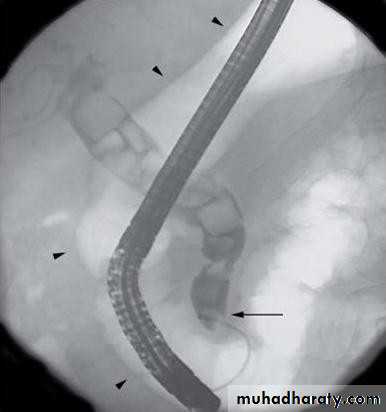

• ENDOSCOPIC RETROGRADE

• CHOLANGIOPANREATOGRAPHY (ERCP)• Side veiwing endoscopie

• Cannulation of ampulla of Vater

• Injection of contrast to visualize the bile

• ducts

• ERCP